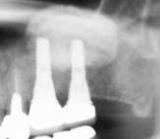

| インプラント治療技術の進歩によって、自分の歯と殆ど見分けがつかないように治療することが可能になりました。しかし、インプラントは決して自分の歯にまさる物ではありません。まず、ご自分の歯を大切にして下さい。 | ![]() |

【術前】 |

【術後】 |